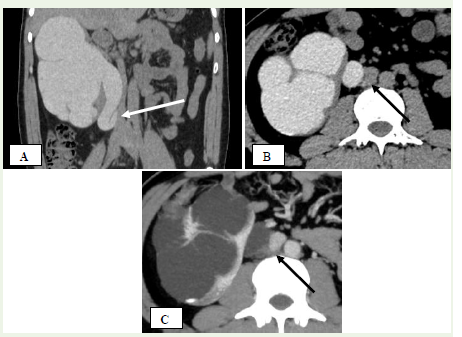

Figure 10 A, B, C: A 26-year-old man with repeated episodes of right flank

pain. (A) Coronal reconstructed image from the excretory phase of contrast-enhanced

CT IVU reveals right-sided hydronephrosis and a characteristic

‘fish-hook’ appearance of the upper ureter caused by its retrocaval path

(white arrow). (B) and (C) Axial CT images during excretory and nephrogenic

phases show the right ureter coursing posterior to the IVC (black arrow).

Figure 11 A 28-year-old man presenting with recurrent right flank pain.

(A) Axial CT image during the excretory phase demonstrates the retrocaval

trajectory of the right ureter (black arrow). (B) Coronal reconstructed image from

the excretory phase reveals hydronephrosis with the upper ureter forming a ‘fishhook’

configuration due to its retrocaval route (white arrow). (C) A 3D-rendered

CT IVU image highlights the same finding—right-sided hydronephrosis and

‘fish-hook’ shaped ureter consistent with a retrocaval course

remain asymptomatic [28].Imaging findings:

Imaging distinguishes two types:Type 1: The ureter crosses behind the IVC near L3 with a characteristic “S” or “fish-hook” deformity and hydronephrosis in over 50% of casesalso known as the low loop retrocaval ureter [Figure 10] [Figure 11]

Type 2: The retrocaval segment crosses at the renal pelvis with a sickle-shaped curve and mild hydronephrosis, which is less common [29].